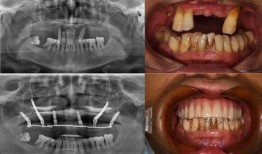

佛山种牙爆料事件视频曝光,揭露行业乱象引发关注

最近佛山那边的种牙事件可是闹得沸沸扬扬的,咱们得好好来聊聊这个话题。你有没有看过那个爆料视频?简直让人瞠目结舌啊!事件回顾:佛山...

2025-11-01 121